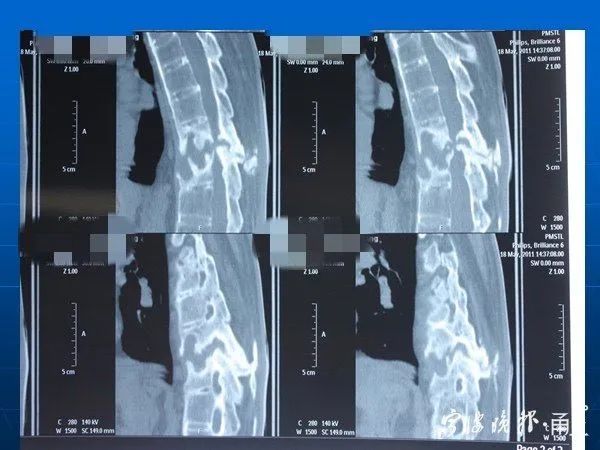

家人急忙把他送到当地医院,后又转送到宁波市第一医院。刘强被诊断为第十胸椎横断性骨折,伤及脊髓神经,导致截瘫。

经过全面的检查发现,刘强患有强直性脊柱炎,且已是晚期,整个脊柱都有严重病变。

刘强的脊柱影像